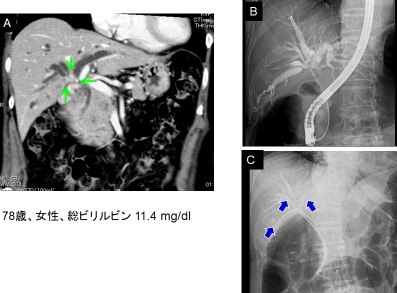

門脈塞栓術後に拡大右肝切除を行った肝門部胆管癌症例

A.入院時造影CTで右胆管優位の肝門部胆管癌を認めました(↓)。

B.C.左胆管のドレナージのみでは減黄できなかったため、3本のERBDを挿入しました(↓)。

右門脈閉塞術後に右門脈は完全に閉塞しており、残肝体積は34%から42%に増大しました。

右肝切除+尾状葉全切除+肝外胆管切除・リンパ節郭清+胆管空調吻合を行いました(手術時間8時間40分、出血量700g、無輸血)。組織学的な治癒切除が得られました。

治療経過と総ビリルビン値の推移を示します。内視鏡的ドレナージにより速やかに減黄しました。

術後は順調で9ヶ月間、無再発生存中です。

治療経過と総ビリルビン値の推移グラフ